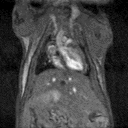

Multimodal imaging combines the strength of MRI with other imaging modalities such as PET and CT. PET provides information on the spatial distribution of molecular signal of interest. In this case MRI confirmed that the absence of tracer uptake in the center of the images was due to the presence of a necrotic core, which appears hyperintense on T2-weighted MR.

Multimodal imaging combines the strength of MRI with other imaging modalities, such as PET and CT. PET provides information on the spatial distribution of molecular signal of interest. In this case MRI confirmed that the absence of tracer uptake in the center of the images was due to the presence of a necrotic core, which appears hyperintense on T2-weighted MR. Image Credit: Scintica Instrumentation Inc